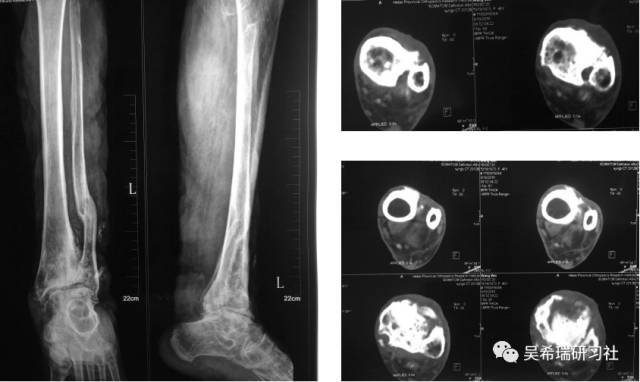

男  43岁 从2米处摔伤  开放性Pilon骨折

TIPS:关节内骨折非跨越关节固定技术一期应用骨水泥 + 开放植骨技术腓骨克氏针固定技术截骨矫形胫骨近端取骨技术